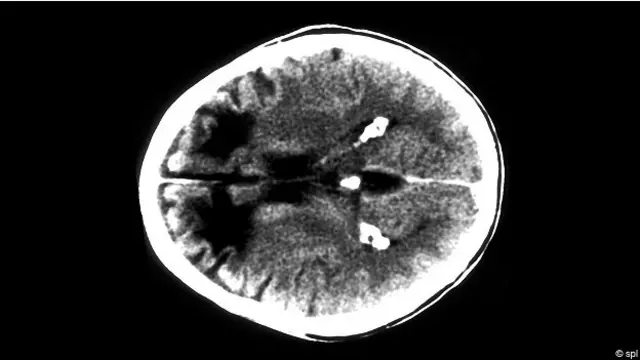

Эти сведения хранились в секрете до тех пор, пока в 2011 году Нидженсон (сам – уроженец Аргентины – Ред.) не обнаружил результаты посмертного сканирования ее скелета, включая рентгеновские снимки черепа, на которых видно, что его сверлили.

Такая операция предполагает иссечение нейронных связей (афферентных и эфферентных волокон) между лобными долями и другими отделами мозга. Ее цель состоит в том, чтобы заглушить эмоциональные реакции пациента.